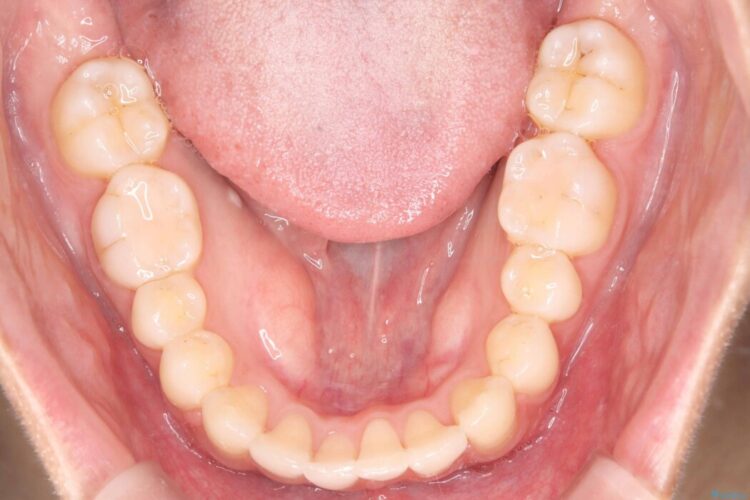

歯のガタつきが気になるとご来院された患者様です。

矯正検査の結果、非抜歯にてワイヤー矯正を行うこととしました。

ガタつきのほかに反対咬合も認められたため、見た目だけでなく嚙み合わせも同時に改善していきます。